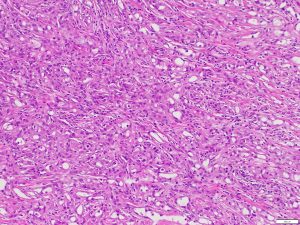

Adenomatoid tumor, arising from the tunica albuginea.

Adenomatoid tumors are benign tumors and accounts for 30% of all paratesticular masses. These tumors can commonly arise from epididymis and less commonly from the tunica albuginea, spermatic cord, or tunica vaginalis. Patients with adenomatoid tumors are commonly in their 30s to 50s. Tumor sizes can range from 0.5 cm to 5 cm. The studies show that the history of injury or inflammation is not related with the diagnosis of adenomatoid tumor from tunica albuginea.

In this patient, macroscopic examination shows a mass that is 1.1 cm in diameter, round shaped, well demarcated borders and involving tunica albuginea. It appears to be an intratesticular mass because it originates from the tunica albuginea.

Immunohistochemical assays with appropriate controls show that tumor cells diffusely express calretinin (as shown), WT1, D240, AE1/3 (as shown), while they are negative for SMA and PAX8. These findings support the above diagnosis.

Adenomatoid tumor, tunica albuginea